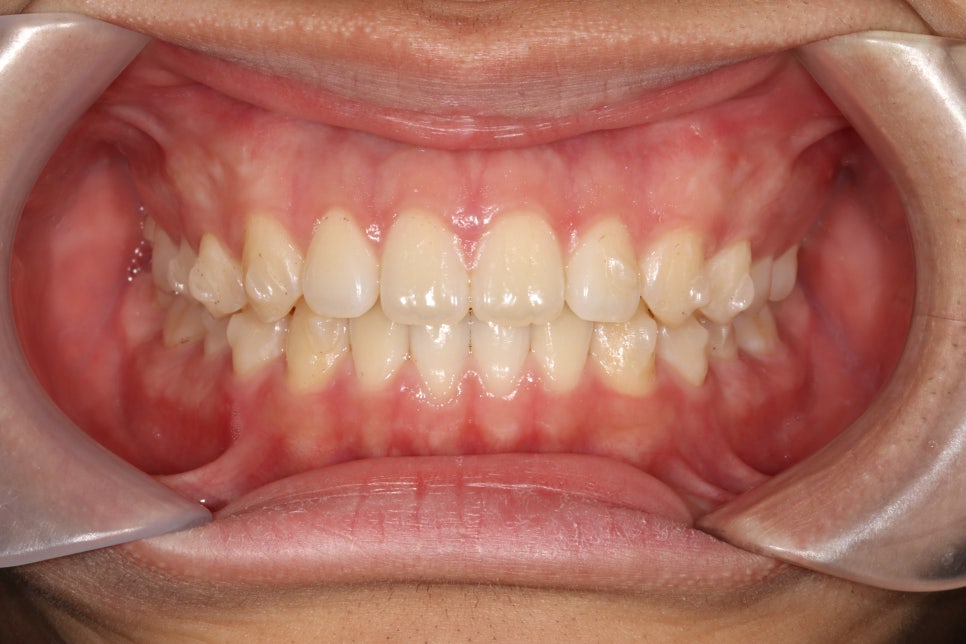

처음 내원하시고 약 4개월이 조금 넘은 기간의 변화입니다.

사실 여기서 끝내도 될 정도라고 하셨지만 제가 재제작한번 하자고 했어요

제 작품이라는 생각에 그냥 보내드릴 수 없죠 ㅎ

재제작을 통해 제 마음에 안들던 교합까지 형성해드리고, 치아배열도 마무리.

공간도 모두 없어지고 배열도 좋아졌습니다